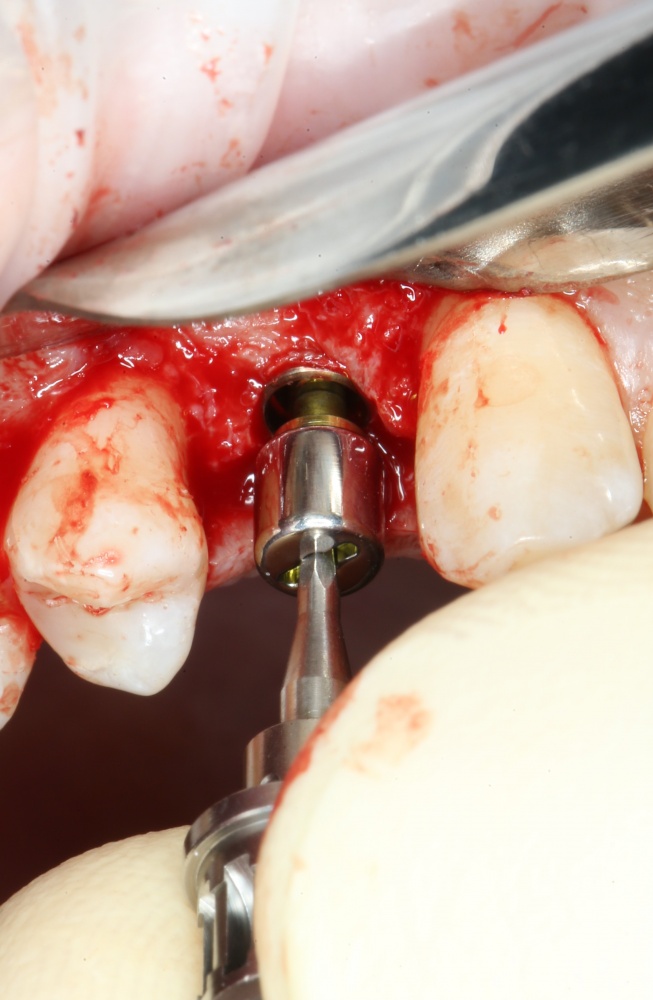

Важный момент! Если вы сделали всё правильно, подготовленная лунка должна кровоточить, а имплантат без вращения должен проваливаться в неё,как минимум, наполовину вне зависимости от его длины:

Поскольку на устанавливаемом нами имплантате уже зафиксирован временный абатмент TempBase, мы используем соответствующий гексагональный ключ 3.4/TB.